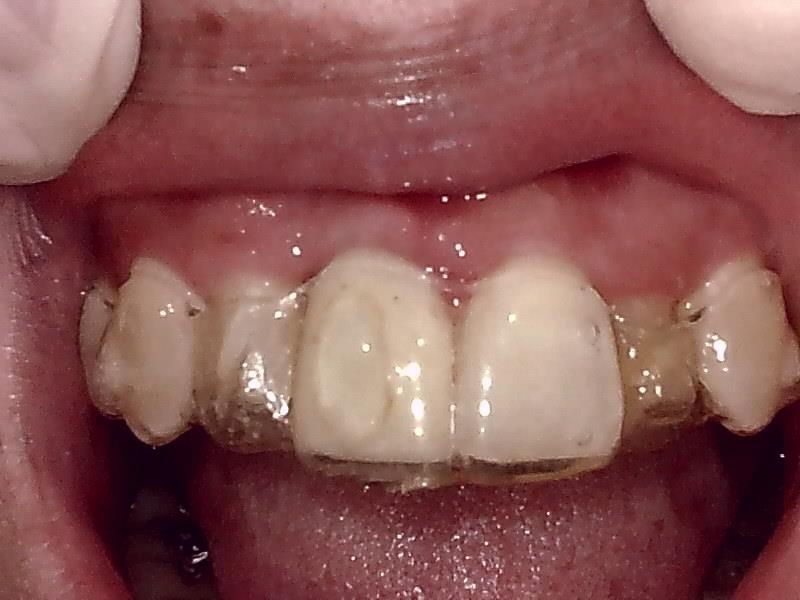

インプラントの上部構造 (右上)

(ジルコニアセラミッククラウン)

術後、インビザライン矯正中よりアライナー装着中

とても経過良好です。

インビザライン矯正中よりアライナー装着している。